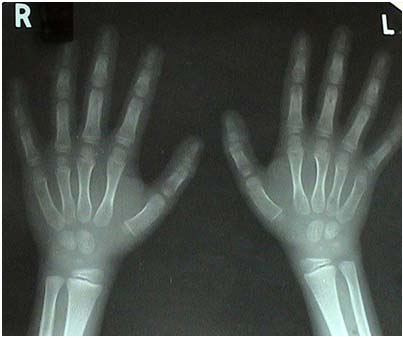

Before the treatment: (May 2002) X-ray of wrist joint showed 4 carpal bones

During the treatment:

September 2003